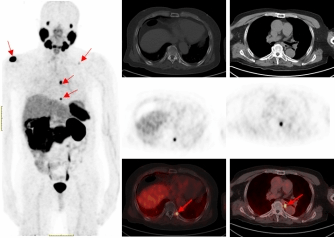

一名75的岁男性患者自2019年确诊前列腺癌后,先后接受过两次内分泌治疗及前列腺癌根治术的综合治疗。在术后两年的复查中发现血PSA持续升高,CT检查和全身骨显像检查均未发现明显异常,医生建议随诊,患者来到脱裤吧

附属医院要求进一步检查。经核医学科68Ga-PSMA PET/CT检查后结果显示,双侧肩胛骨、左侧第9后肋、第2腰椎及纵隔淋巴结均已存在癌症转移。